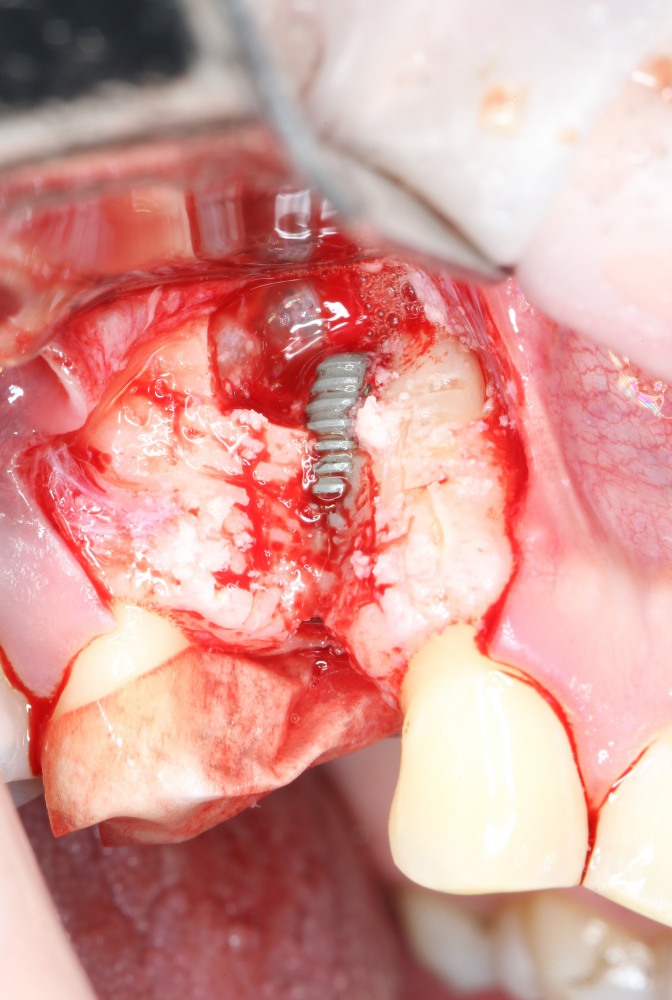

Простой. Надежный. Дешевый. Способ остеопластики.